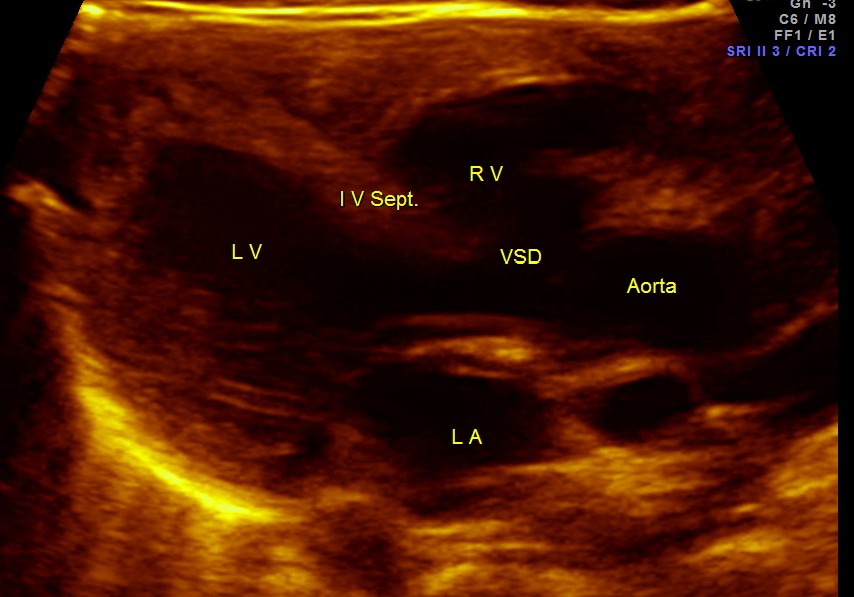

The following pictures are of the heart of the child .

The IVS straddling the aorta is prominently seen ; The RV is mildly dilated . Though the pulmonary artery was difficult to comment on , I would still go with TETRALOGY OF FALLOT with RENAL DYSPLASIA , which makes it complicated.